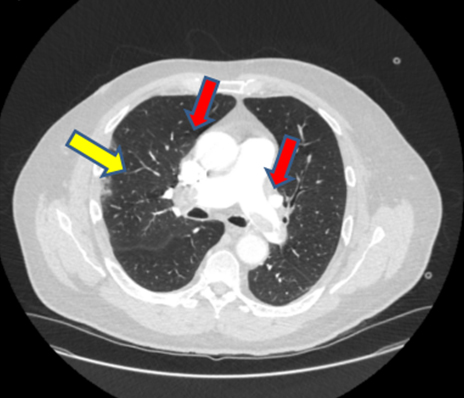

As the patient met the criteria for COVID-19, a nasopharyngeal swab was taken and a reverse transcription-polymerase chain reaction (RT-PCR) test for SARS-CoV-2 was positive. Computed tomography (CT) pulmonary angiogram (CTPA) showed significant bilateral pulmonary emboli with peripheral right-sided ground glass opacification suspicious for either COVID-19 or related to the pulmonary infarction (Figure 3). It was decided that the rise in troponin levels and ECG changes were likely to be secondary to APE rather than NSTEMI. Moreover, the right heart strain on CTPA made this more likely (Figure 4).

Figure 3: CT pulmonary angiogram red arrows indicate pulmonary emboli; yellow arrow shows ground-glass appearance.